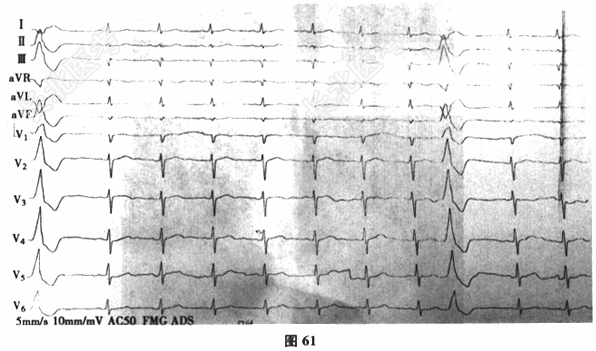

- 多项选择题3.[提示]入院后持续监测,生命体征平稳, 经对症治疗症状逐渐缓解。进一步检查,下肢深静脉多普勒超声: 右侧腘静脉、胫后静脉多发血栓形成。肺动脉CTA(图62~图65)示双肺动脉分支多发栓塞。冠脉CTA示冠脉多处钙化斑块,前降支中段轻度狭窄。BNP36.8pg/ml(正常0~100pg/ml)。TNI<0.05ng/ml(正常0~0.4ng/ml)。动脉血气分析: 氧分压63mmHg,二氧化碳分压28.7mmHg。